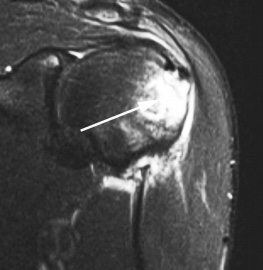

(Слева) Корональная МР-артрограмма: визуализируется отслаивание хряща головки плечевой кости. Контрастный препарат распространяется между суставным хрящом и подлежащей костью параллельно суставной поверхности. Выше отмечается локальный дефект хряща, через который затекает контрастный препарат.

(Справа) Аксиальная Т1FS МР-артрограмма, молодой пациент, занимающийся армрестлингом: определяется отслаивание хряща. Следует отметить, что передняя губа интактна.